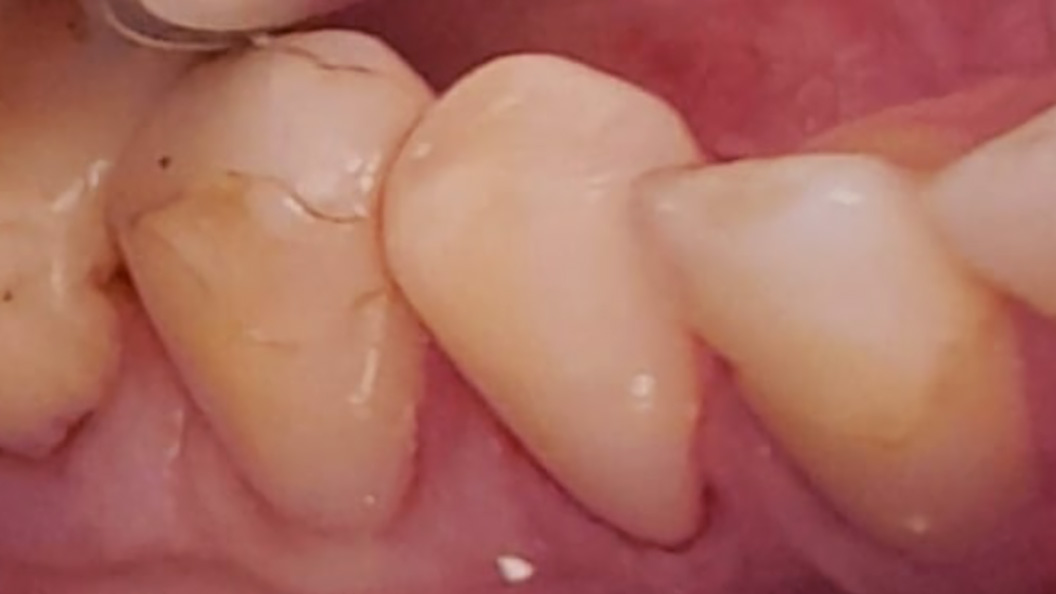

Пациентка обратилась к стоматологу-терапевту с проблемой выпадения пломбы из премоляра нижней челюсти. Её также беспокоила резкая боль в зубе, которая возникает после принятия холодной пищи и напитков, но быстро проходит. Осмотр и диагностика позволили выявить у пациентки наличие глубокого кариеса зуба 44. Ей предложено лечение с установкой светоотверждаемой пломбы.

Ход лечения:

- очистка зуба от налёта и удаление отмерших тканей;

- введение анестезии;

- установка и застывание светового композита Эстелайт;

- полировка и шлифовка зуба.